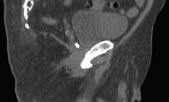

One week after transponder placement, a non-contrast CT scan, Figures 3a and 3b, is obtained under the supervision of the treating radiation oncologist according to the following parameters (FOV = 48 cm; matrix = 512 x 512): from 2 cm above the iliac crest to 2 cm above the femoral heads with 1 cm slice thickness; from 2 cm above the femoral heads to the bottom of the ischial tuberosities using 3 mm slice thickness; and from the bottom of the ischial tuberosities to 12 cm caudal using 1 cm slice thickness. The resultant images are transferred to a treatment planning workstation where a CT-MRI fusion is performed employing chamfer matching and maximization of mutual information techniques. Once the fusion is complete, the critical structures are contoured, including the prostatic fossa, bladder and rectum, as well as the femoral heads, skin and small bowel. The transponder beacons are also identified during this process and their location is registered by the software. An intensity-modulated radiation therapy (IMRT) plan is generated that will cover the planned target volume while limiting the dose to the bladder and rectum. The stored location of the beacons is where the transponders are expected to be found during daily RT treatments, and the Calypso system compares the expected location to the actual location of the transponders prior to the beginning of each treatment session. By convention, a greater than 5 mm intrafraction movement in any direction would result in a cessation of the daily fractionated dose and a realignment of the Calypso system. In order to realign the system, a repeat CT scan must be performed to re-contour the critical structures in relation to the new location of one of the transponders.

Figure 3b. Sagittal CT image of electromagnetic transponder beacon in prostatic bed.